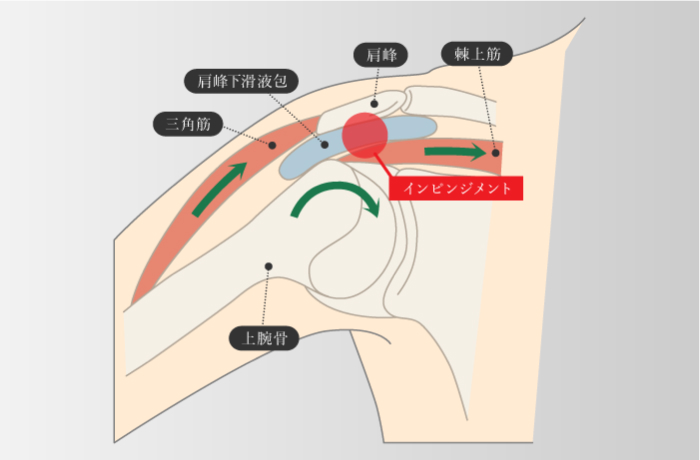

インピンジメント症候群

-

腱板断裂などのはっきりとした損傷を伴わずに肩の痛みを起こす疾患の一つで、肩のこすれや挟まりこみ、骨の衝突などが原因

インピンジメント症候群・FAI

大腿骨寛骨臼インピンジメント

-

先天性のものと後天性のもの2種類があり、先天性の構造要因には、大腿骨頭や寛骨臼の形成不全がある。 また、後天性の構造的要因の代表例には、変形性股関節症があり、軟骨の摩耗や骨棘の形成により、股関節のインピンジメントが発生する。